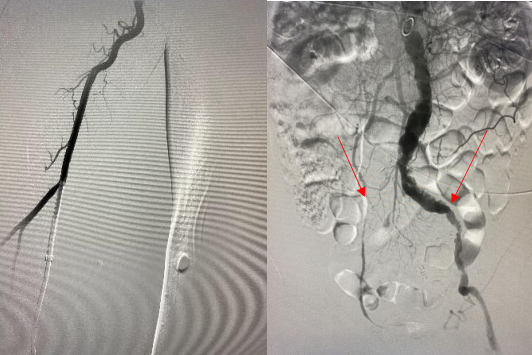

头颈部血管造影提示:患者为右侧颈内动脉极重度狭窄合并右侧大脑中动脉闭塞。

由远及近,优先开通右侧大脑中动脉恢复颅内血流,再行右侧颈内动脉起始部支架植入血管成形,顺利开通闭塞血管,颅内血流恢复。